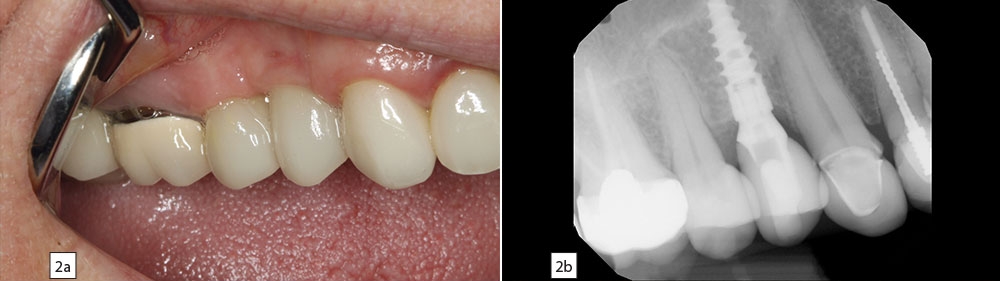

Figures 2a, 2b: Following integration of the implant, a screw-retained crown was delivered, with excellent tissue preservation in the area of the restoration.

PG: It was about two years ago for a patient who needed to replace a maxillary first bicuspid. This patient had a failing root canal and was not willing to cut down a canine and another premolar to have a bridge placed. So this was an ideal site for an implant. It’s actually a good area for beginners to place implants because you’re out of the zone of the maxillary sinus and you’re not near any major nerves. I extracted the tooth, did a site preservation graft, came back four months later and placed the Hahn implant. Four months after that, we came back and restored the implant with a screw-retained crown, and the patient is doing great. This was a soft bone area, and the aggressive threads allowed me to get great primary stability.